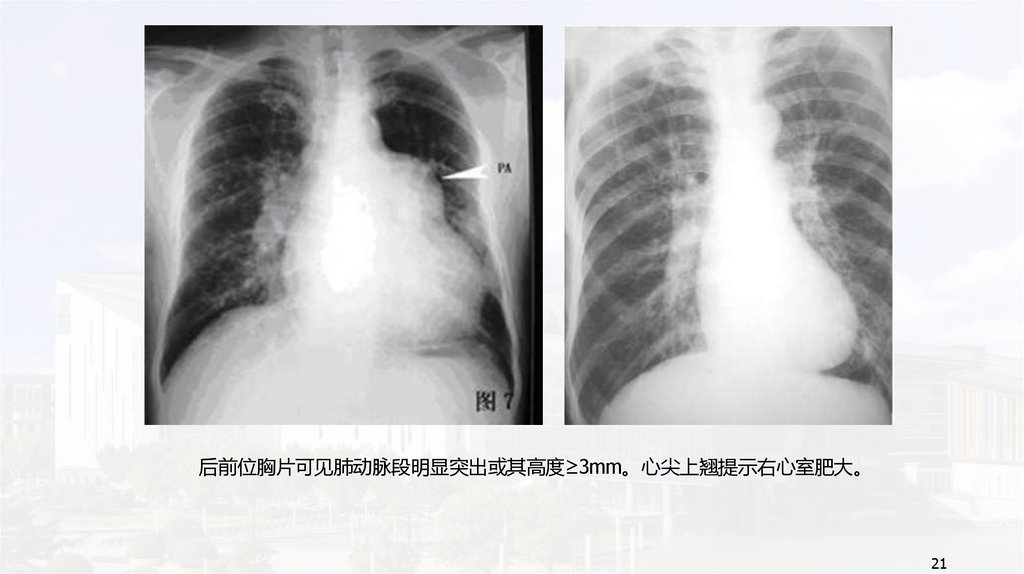

后前位胸片可见肺动脉段明显突出或其高度≥3mm。心尖上翘提示右心室肥大。

21